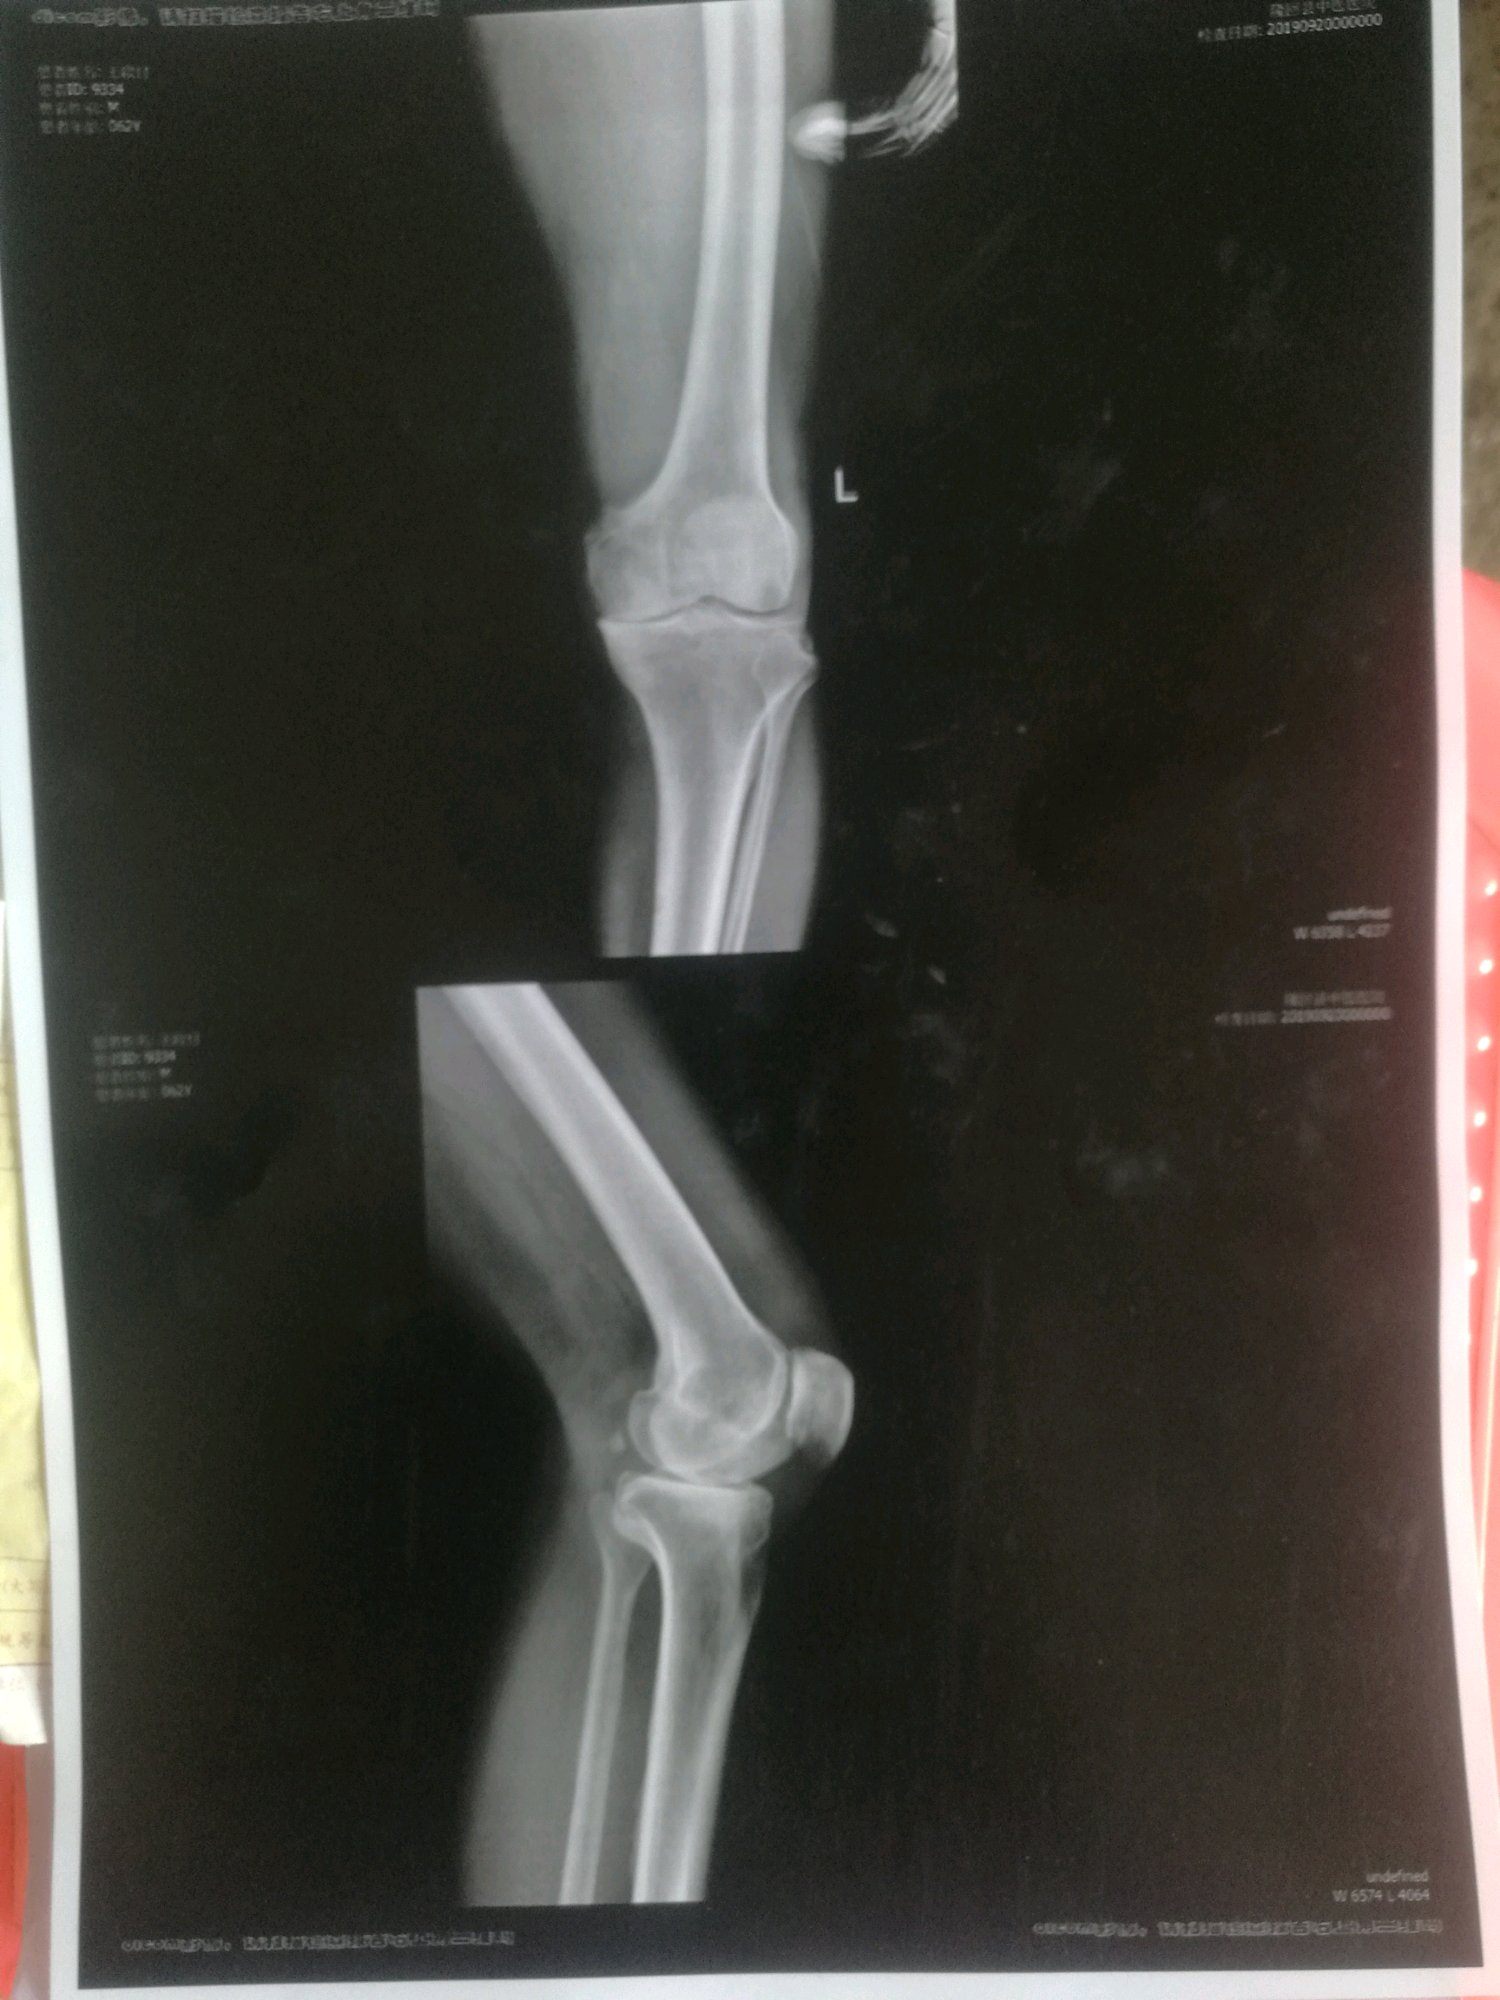

父亲拍片 [走路腿痛] 求各位给点指导意见 不甚感激